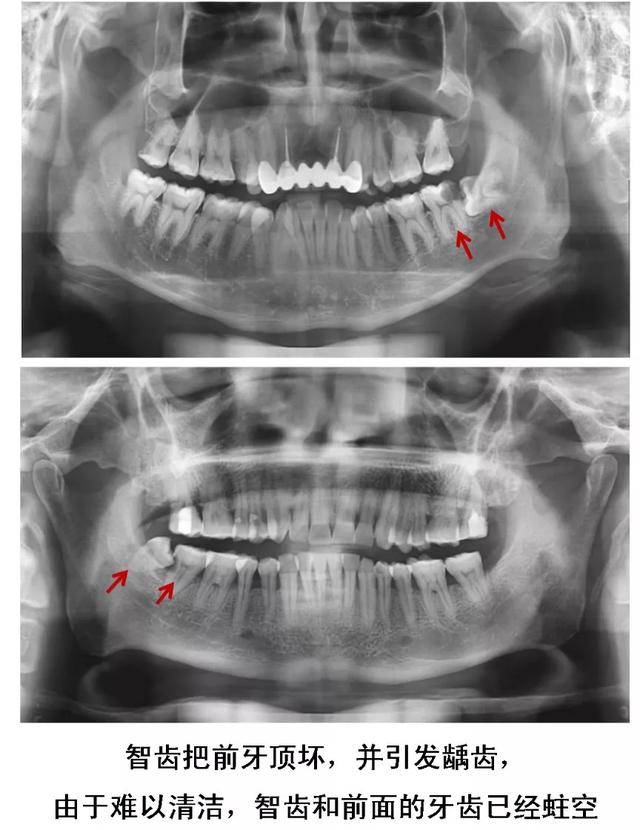

1、易患龋齿的智齿

智齿因为长在最里面,平时刷牙时容易被忽视,也很难清洁到位,经常会发生蛀牙,可能还会牵连邻牙。

2、长歪的阻生智齿

当智齿没有足够空间生长,脱离“轨道”,与邻牙之间产生缝隙,容易嵌塞食物,滋生细菌,引起蛀牙。

或是智齿生长的方向正好顶住邻牙,时间久了不仅会把邻牙顶坏,龋坏进一步发展会造成牙髓炎。